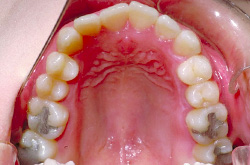

上あご・正面・下あご

before

after